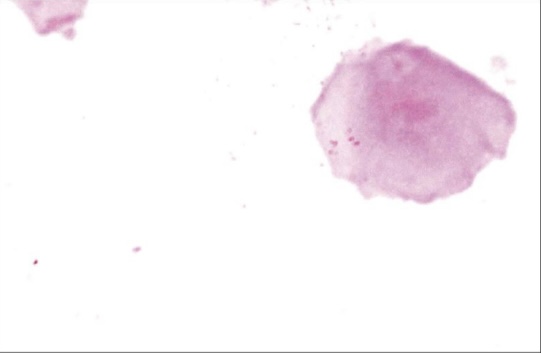

Apoptosis in necrosis